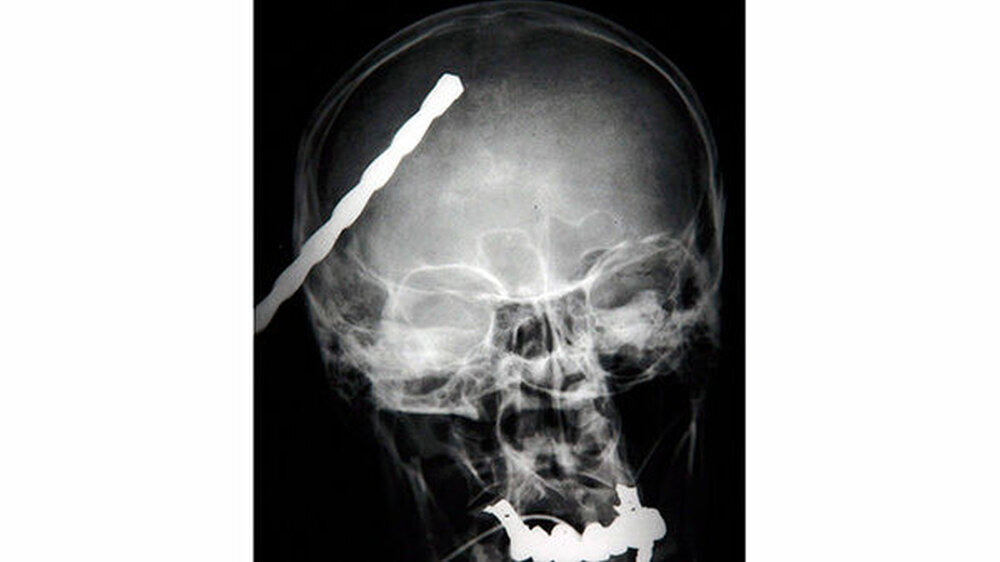

Vom Bohrer im Kopf bis zum Schlüssel in der Kieferhöhle: Die MKG-Chirurgen der Charité haben ausgewählte Patientenfälle mit Fremdkörpern im Gesicht zusammengestellt. In unserer Fotostrecke finden Sie die eindrucksvollen Aufnahmen.